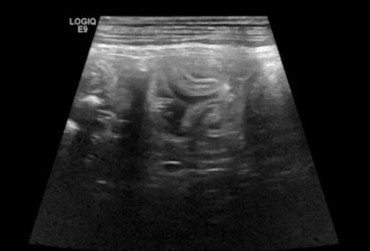

Określenie „rozpoznanie cioci Minnie” pochodzi ze Stanów Zjednoczonych i jest żartobliwym określeniem rozpoznania patognomonicznego, stosowanym głównie przez radiologów. Zwrot ten stał się popularny w latach 90. XX w. za sprawą strony internetowej o takim tytule. Obecnie to określenie stosuje się również w metodologii nauczania klinicznego. W artykule przedstawiono przypadki rozpoznań „cioci Minnie” z własnego archiwum ultrasonografii jamy brzusznej małych zwierząt.